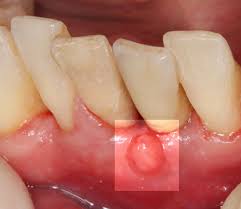

Das hintere Zahnfleisch also das Zahnfleisch hinter den Schneidezähnen ist auch irgendwie geschwollen ist auch etwas rot aber wie es aussieht nur äußerlich die Zähne selbst verursachen keine Schmerzen eben nur dieser Druck und das Gefühl dass sie zu groß sind. Der Wange ist abhängig davon inwieweit sich die Zahnwurzel entzündet hat. Meist bildet sich in dieser Zeit eine Beule am Zahnfleisch in direkter Nähe zum betroffenen Zahn.

Die betroffenen Stellen fühlen sich meist wund an brennen oder sind gerötet und geschwollen Ödem Flüssigkeitsansammlung im Gewebe. Die hormonell bedingte oberflächliche Zahnfleischentzündung Gingivitis zeigt sich als geschwollenes oft auch gerötetes Zahnfleisch das leicht blutet ich habe hinter den oberen Schneidezähnen also direkt in der Mitte eine Entzündung Schwellung. Wenn es geschwollen und entzündet ist wird es rot.

Oft fühlt sich geschwollenes Zahnfleisch gereizt oder empfindlich an. Diese Stelle liegt oben im Mundraum und direkt hinter den Zähnen.